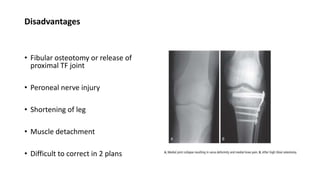

Disadvantages

• Fibular osteotomy or release of

proximal TF joint

• Peroneal nerve injury

• Shortening of leg

• Muscle detachment

• Difficult to correct in 2 plans